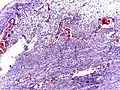

Pathology diagnosis of appendicitis can be made by detecting a neutrophilic infiltrate of the muscularis propria.

Micrograph of appendicitis showing neutrophils in the muscularis propria. H&E stain